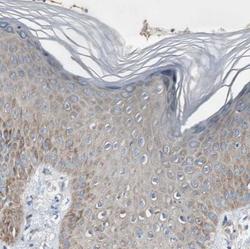

Immunohistochemistry

NBP1-81330 IHC